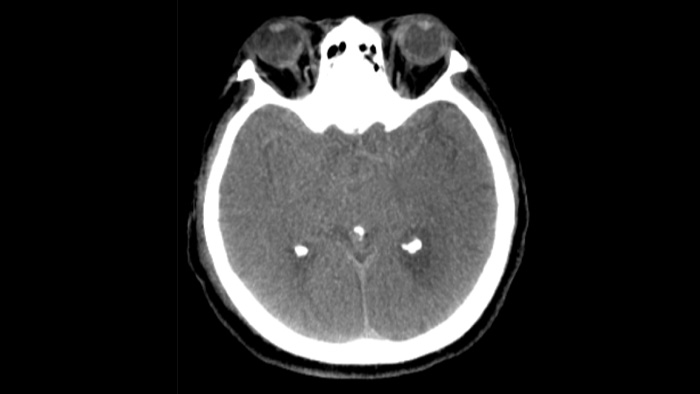

Verwenden Sie die CT-artigen Bilder der Neuro Suite zur Beurteilung des Behandlungserfolgs und Überprüfung auf Blutungen.

Die CT-artigen Bilder der Neuro Suite helfen bei der Beurteilung des Behandlungserfolgs und der Erkennung von Blutungen.

Nach der Schlaganfallbehandlung muss verifiziert werden, ob das gesamte Gerinnsel entfernt wurde und ob Blutungen vorliegen. Idealerweise finden diese Kontrollen statt, während sich der Patient noch im Interventionslabor befindet.

Hochwertige DSA-Visualisierungen ermöglichen es Ihnen, zu beurteilen, ob das Gerinnsel vollständig entfernt wurde und ob sich Teile davon distal in das Gehirn verteilt haben. Sie können die Wiederherstellung des Blutflusses zur Penumbra verifizieren und eine Überprüfung auf periprozedurale Blutungen vornehmen.